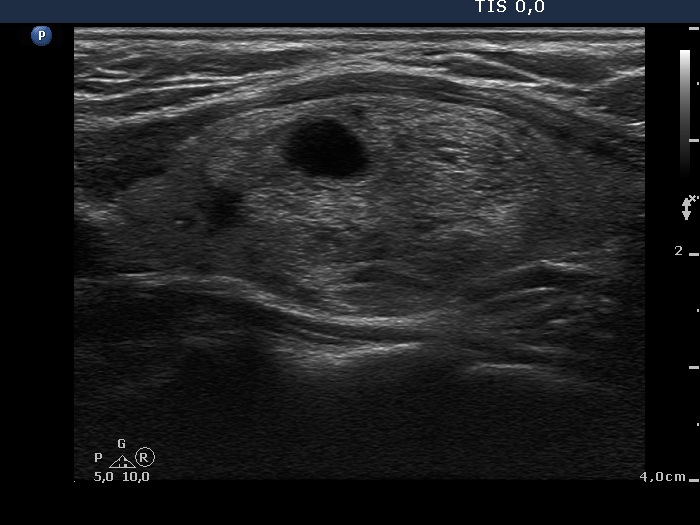

Benign nodular hyperplasia - Case 51. (ultrasonographic picture 6)

Left lobe, longitudinal scan.